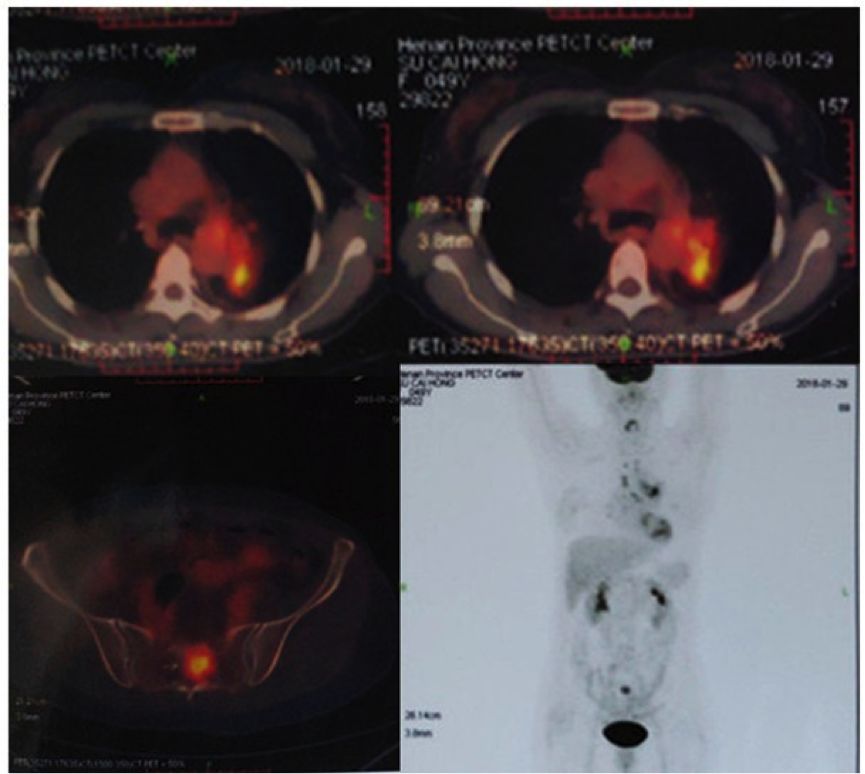

患者诊断IVA期伴ALK阳性,故于2018年2月开始克唑替尼治疗,治疗过程耐受性良好,疗效评价PR。并且患者于2018年9月因腰骶部疼痛行骶骨转移灶放疗。

图4.患者接受克唑替尼治疗时候的基线情况(2018-01)、以及治疗随访胸部CT影像

患者于2018年9月初开始出现间断头疼、失语、反应迟钝,并进行性加重,但头颅MRI(2018.09.10)脑实质未见明显转移,予以对症支持治疗。

图5. 2018年9月10日患者头颅MRI检查影像